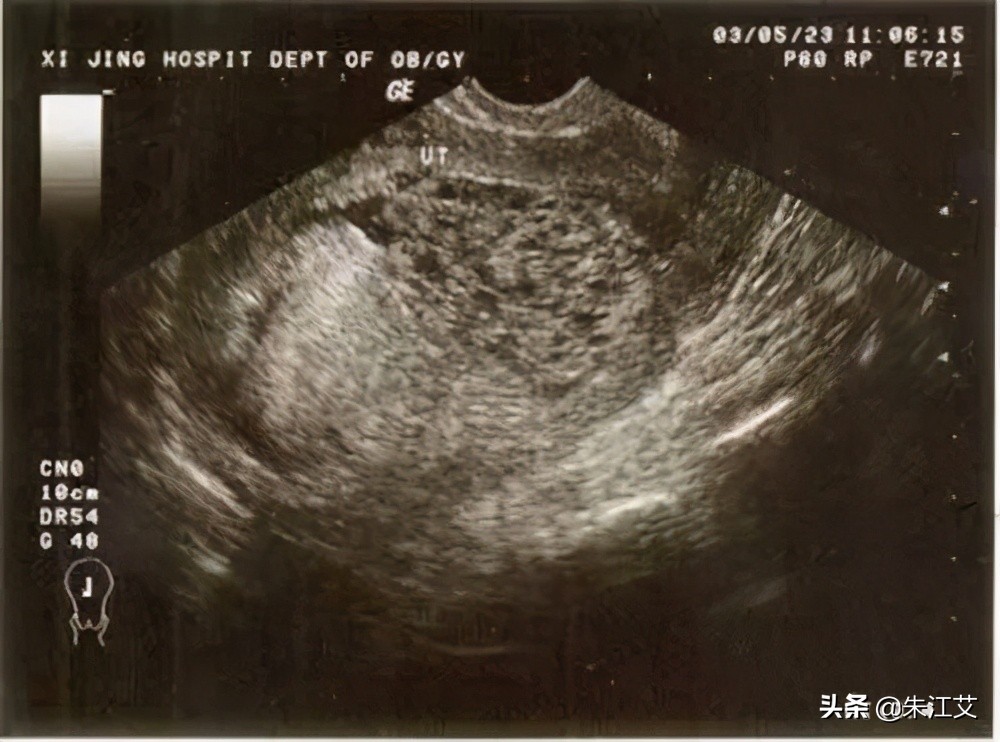

4. 葡萄胎出血

1)葡萄胎出血一般是怀葡萄胎的首发者症状。如果是葡萄胎一般还伴随较严重的孕吐反应。还伴随下腹疼痛的情况。

2)如果是部分性葡萄胎一般怀孕50天以上能查出,完全性葡萄胎怀孕44天左右结合彩超,HCG情况能判断出。